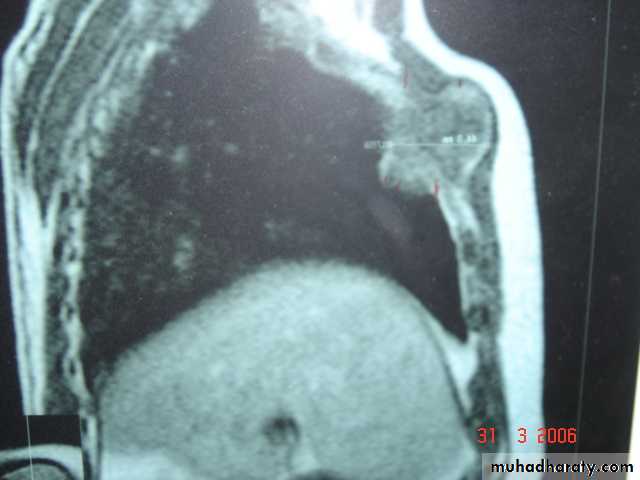

• Superior sulcus tumor of Pancoast It is a low grade epidermoid carcinoma that grows slowly and metastasize late, infiltrates and involves lower root of Brachial plexus, intercostal nerves , Cervical sympathetic nerves & eroding the upper ribs ,producing pain in the shoulder & Horner's syndrome .